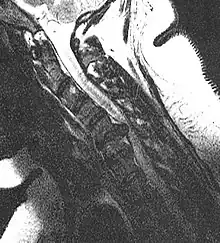

Cervical disc herniation

Herniated disc at C6–C7 level

Cervical disc herniations occur in the neck, most often between the fifth and sixth (C5–6) and the sixth and seventh (C6–7) cervical vertebral bodies. There is an increased susceptibility amongst older (60+) patients to herniations higher in the neck, especially at C3–4.[22] Symptoms of cervical herniations may be felt in the back of the skull, the neck, shoulder girdle, scapula, arm, and hand.[23] The nerves of the cervical plexus and brachial plexus can be affected.[24]

• Magnetic resonance imaging is the gold standard study for confirming a suspected LDH. With a diagnostic accuracy of 97%, it is the most sensitive study to visualize a herniated disc due to its significant ability in soft tissue visualization. MRI also has higher inter-observer reliability than other imaging modalities. It suggests disc herniation when it shows an increased T2-weighted signal at the posterior 10% of the disc. Degenerative disc diseases have shown a correlation with Modic type 1 changes. When evaluating for postoperative lumbar radiculopathies, the recommendation is that the MRI is performed with contrast unless otherwise contraindicated. MRI is more effective than CT in distinguishing inflammatory, malignant, or inflammatory etiologies of LDH. It is indicated relatively early in the course of evaluation (<8 weeks) when the patient presents with relative indications like significant pain, neurological motor deficits, and cauda equina syndrome. Diffusion tensor imaging is a type of MRI sequence used for detecting microstructural changes in the nerve root. It may be beneficial in understanding the changes that occur after herniated lumbar disc compresses a nerve root, and might help in differentiating the patients that need surgical intervention. In patients with a high suspicion of radiculopathy due to lumbar disc herniation, yet the MRI is equivocal or negative, nerve conduction studies are indicated.[43] T2-weighted images allow for clear visualization of protruded disc material in the spinal canal.